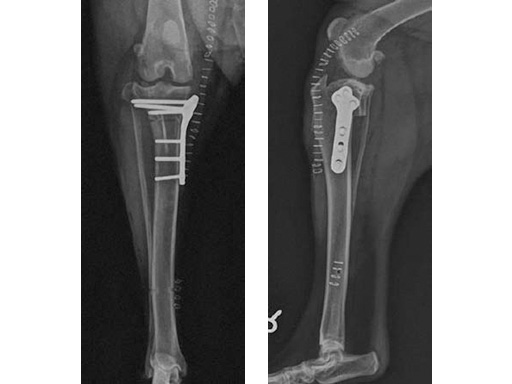

The tibia plateau leveling osteotomy (TPLO) procedure dynamically eliminates cranial tibial subluxation associated with cranial cruciate ligament (CCL) disease in the dog, and thereby stabilizes the knee joint during locomotion. CCL rupture in the dog is similar to ACL injury in humans.

The standard saw and jig are designed specifically for use when performing tibial plateau leveling osteotomy to assist with location, guidance, initiation, and stabilization of the radial saw cut in medium and large breed dogs.

The jig and saw guides can be used bilaterally (for right or left tibiae). Specially designed hinge and saw guide screws within the jig resist loosening under vibration. The hardened steel jig pin screws resist stripping. The saw guides can be positioned in multiple positions along the jig and the jig arm position can be adjusted to allow for optimal placement of the osteotomy. The saw guides are available in three radii of 24 mm, 27 mm, and 30 mm to match the saw blade size selected for an individual patient. The instruments can be easily disassembled for cleaning, and are made of medical grade stainless steel.